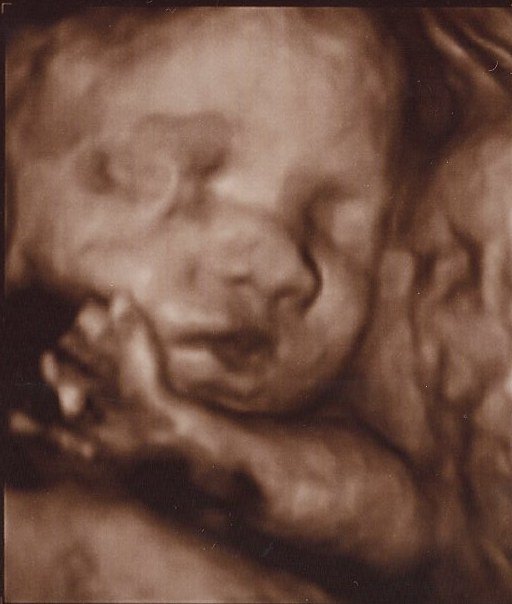

Det er så vildt at være til 3D scanning, det er som om, man er gravid på en helt anden måde bagefter

Ja, virkelig! Det er en hel anden måde at forholde sig til den lille på! Men når man ser billederne synes jeg man tænker "iih hun er stor", men hun er jo i virkeligheden stadig lillebitte. Lidt skægt